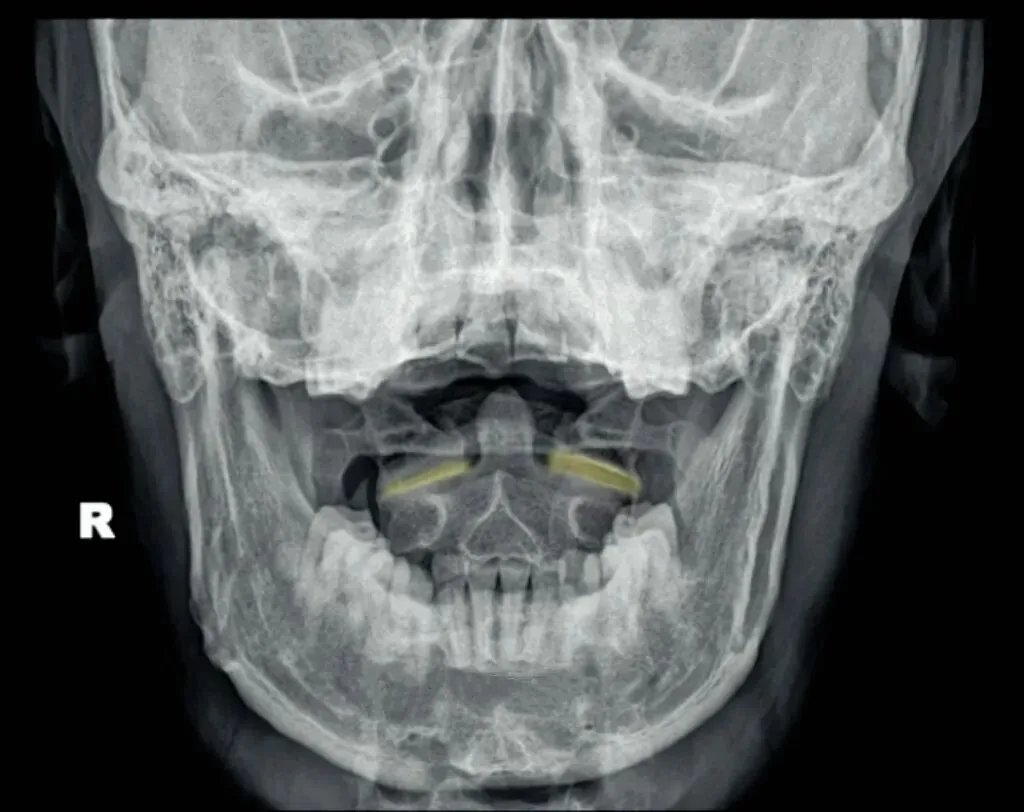

十张口是指寰枢椎的结构和位置关系,我们主要观察寰齿间隙和寰枢关节间隙及寰椎侧块的大小,来判断寰枢关节有无脱位的情况。

首先是寰齿间隙,如果枢椎与颈三的棘突位于同一条直线,

那么寰齿间隙哪边宽,就代表寰椎向哪边发生了侧方移位。

如果不在一条直线上,那就代表枢椎也有侧向的移动或旋转。

接下来是寰枢关节间隙,也称寰枢外侧关节,主要看两侧间隙是否等大,

如果一边宽一边窄,就代表寰椎向窄的一方发生了侧向倾斜。

再下来看寰椎侧块的大小,正常情况下侧块两边的宽度是等大的,

如果哪边侧块变大,就代表哪边的侧块向前方发生了旋转。